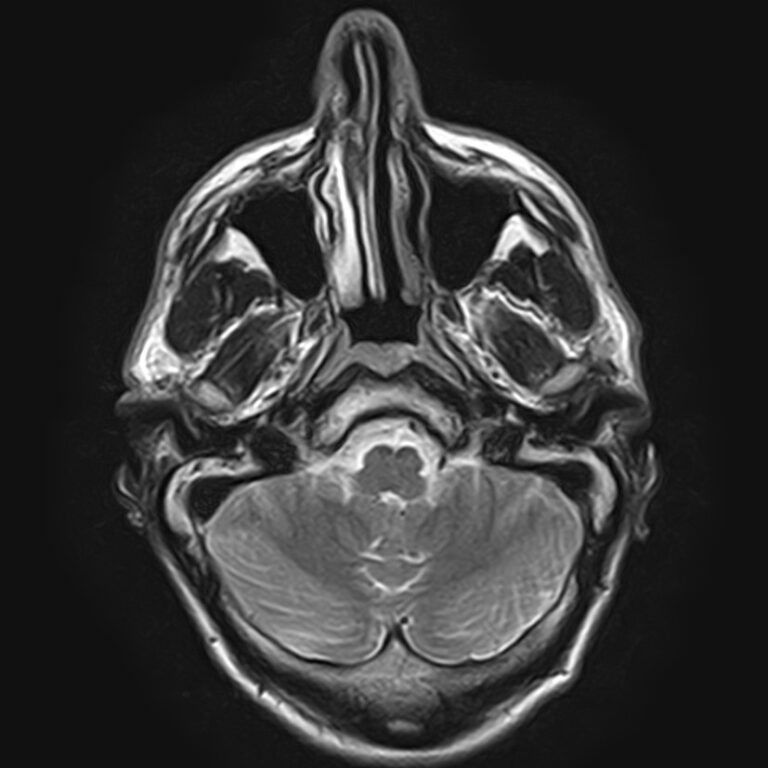

Височно-нижнечелюстной сустав является парным комбинированным суставом и имеет сложное строение. В него входят суставные ямки височной кости, суставные головки нижней челюсти и расположенные между ними хрящевые пластинки – мениски, выполняющие роль амортизаторов.

Чаще всего дисфункция височно-нижнечелюстного сустава обусловлена внутренним повреждением, смещением мениска и суставной головки нижней челюсти. Для определения степени смещения внутрисуставных структур выполняется функциональная проба с проведением МРТ в двух положениях:

Магнитно-резонансная томография является наиболее точным и эффективным методом диагностики поражения височно-нижнечелюстных суставов, так как позволяет получить детальную информацию о состоянии не только костей, но и связочного аппарата, хрящей, менисков, жевательных мышц, окружающих мягких тканей.

В клинике «Доступная медицина» можно пройти исследование МРТ височно-нижнечелюстного сустава на высокотехнологичном оборудовании. Клиника располагает новейшим томографом экспертного класса TOSHIBA VANTAGE TITAN 1,5 Тесла, который благодаря высокой индукции магнитного поля позволяет получать изображения исследуемой зоны в мельчайших подробностях. Томограф производит послойное сканирование области сустава и околосуставных мягких тканей, затем с помощью цифровых приложений преобразует полученные данные в трехмерные изображения превосходного качества.

При проведении магнитно-резонансной томографии на изображениях визуализируются: височная кость, головка мыщелкового отростка нижней челюсти, суставная щель. Помимо костных структур МРТ позволяет оценить состояние мягких тканей – внутрисуставного диска и связочного аппарата височно-нижнечелюстного сустава, жевательных мышц.